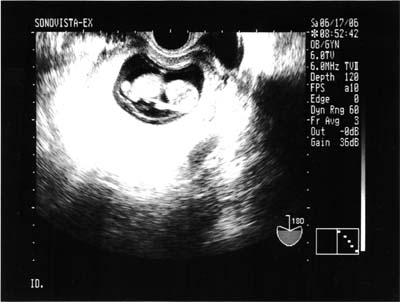

| 2006年5月19日(金) |

| 6w5dでの診察。 胎嚢は30.7mmまで大きくなってました。 中に胎芽が確認出来て、大きさはだいたい3mm位とのことでした。 心拍も確認出来ました。 7w5dになってるけど、胎嚢の大きさから計算された週数なのかな。たぶん。 |